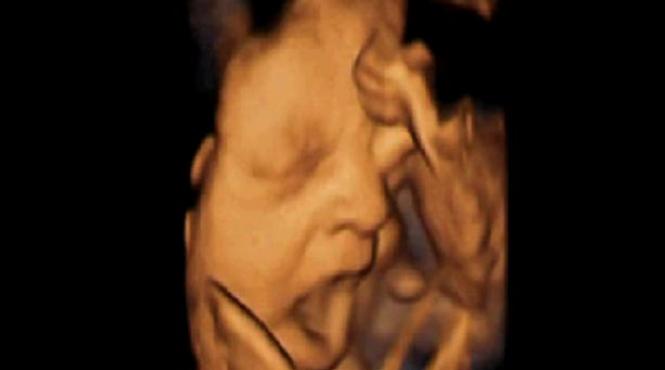

Imagini ULUITOARE: Un fetus cască şi se freacă la ochi în pântecele mamei lui (VIDEO)